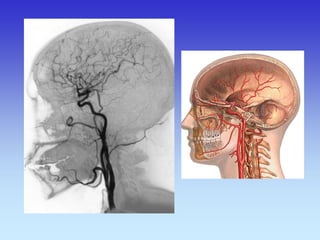

METODE PRIKAZA KRVNIH ŽILA

•UZ-DOPPLER

•DSA

•CTA

•MRA

B-mod i obojeni Doppler karotidne arterije

VASKULARNA OPSKRBA WILLIS-ijev prsten

a. cerebri ant.

a. cerebri media

a. cerebri post.

VASKULARNA OPSKRBNA PODRUČJA